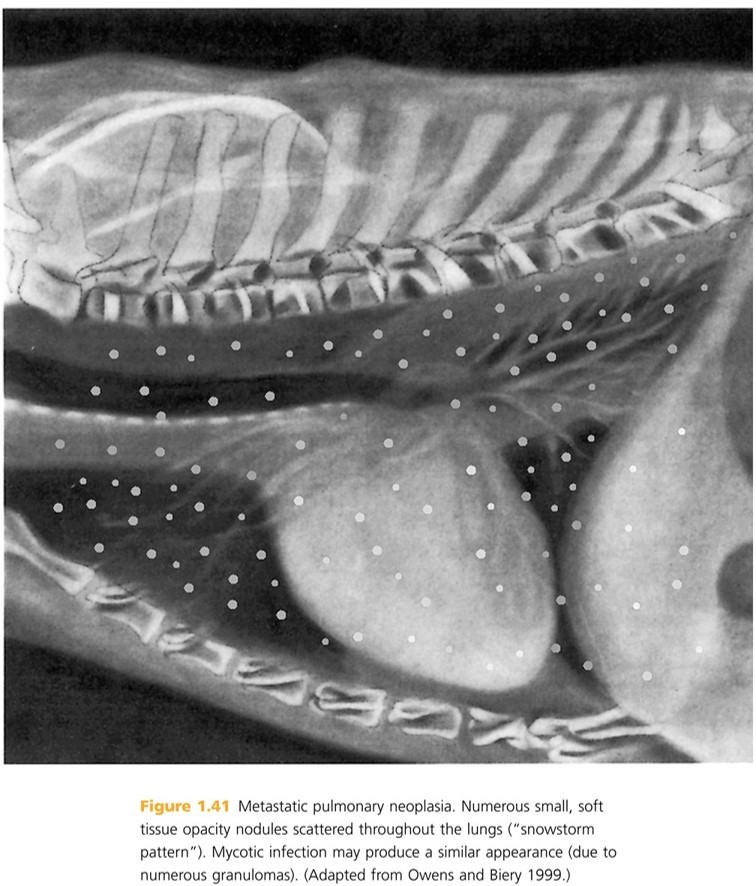

DDX for Numerous nodules scattered throughout lungs (snow-storm pattern)?

Metastatic neoplasia

Infection (especially mycotic)

Pulmonary lymphoma

Eosinophilic pneumonia